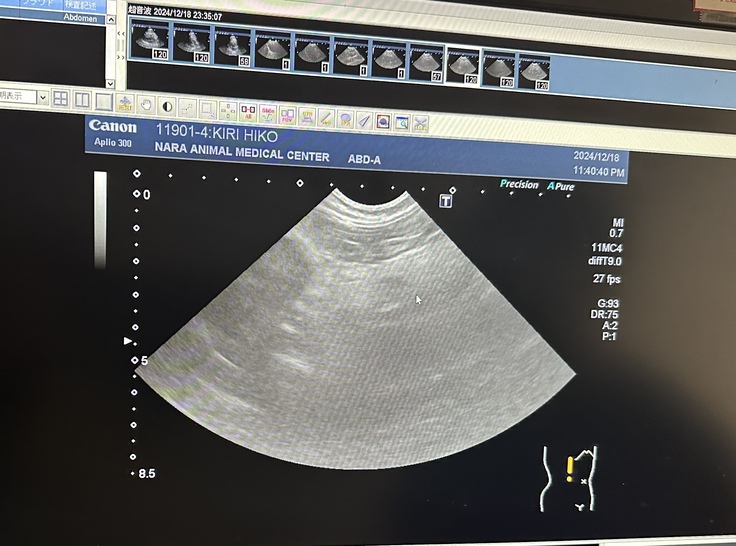

採血とエコー検査の結果『急性膵炎』と診断され、入院になりました。

5日前から膵炎発症し、相当お腹が痛かったでしょうと。詳しい採血結果を待たないと確定診断できないそうですが、膵臓の周囲が肥厚しているので膵炎に間違いないということで治療開始して頂きました。